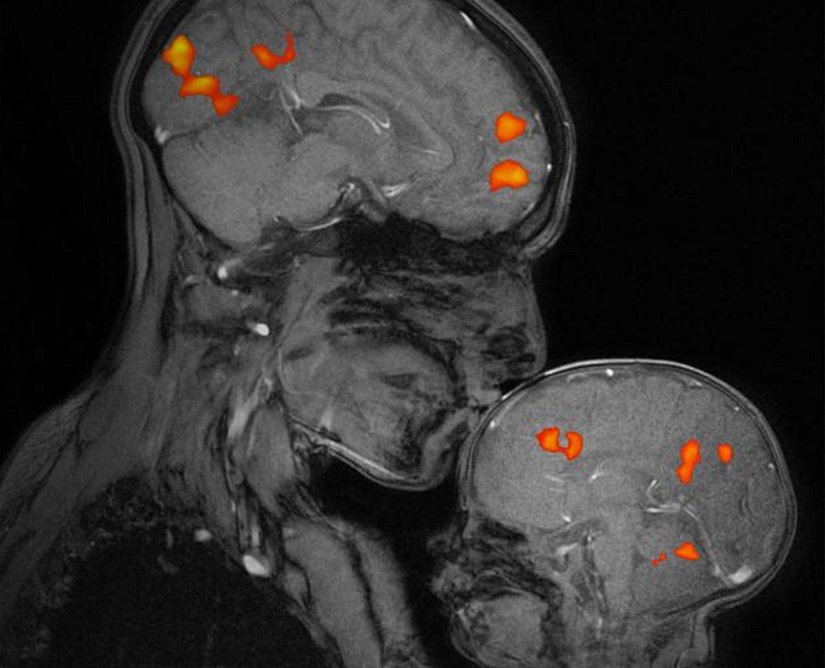

Anne-Bebek ikilisi arasında erken dönemde gelişen bu hayati bağ, beyin görüntüleme çalışmalarıyla da desteklenmeye devam etmektedir. Profesör Rebacca Saxe, bebeğini tutar ve öperken, bebekte oksitosin hormonunun seviyesinin arttığını tespit etmiştir. Oksitosin hormonunun çiftler arasındaki bağlanmayı, başkalarının duygularını anlamayı, göz teması kurma gibi sosyal davranışları arttırdığı ve stresin azalmasında etkili olduğu bulunmuştur.

Swain, bebeğinin ağlamasını duyan annede bilinçli düşünmeden sorumlu frontal korteks ile duygusal hafızanın oluşumunda önemli bir role sahip amigdalada artan nöral aktivite tespit etmiştir.[6] Aynı zamanda, bebeğinin ağlamasını duyan babada duyguların ve duygusal davranışların düzenlenmesinde etkili anterior singulat korteks, göz retinasından gelen bilgileri alıp yorumlayan görsel korteks ile öğrenme ve bellek becerileriyle ilişkili limbik sistemin bir parçası olan parahipokampal girusta artan nöral aktivite tespit etmiştir. Bu bulguları ise, Winnicott’un "birincil annelik tasası" ile ilişkilendirmiştir.